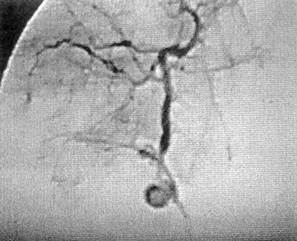

Рис. 15. Ангиогепатография больного Ч., 30 лет. В бассейне правой печеночной артерии — ее передневерхнего сегмента — визуализируется гематома диаметром 2 см

пичная резекция правой доли печени, наложена холецистостома, ушита рана почки, диафрагмы, грудной стенки, дренирована плевральная и брюшная полости. Хирург использовал комбинированный доступ — срединный разрез дополнил подреберным, справа 21.05 санавиацией больной доставлен в клинику. Состояние тяжелое, бледен, склеры субиктеричны, живот умеренно вздут, болезненный, печень выступает из-под реберной дуги на два поперечника пальца. Стул 2 раза в сутки; кал неоформленный, черного цвета. Гипертермия. На обзорной рентгенограмме живота отмечено высокое стояние правого купола диафрагмы. Наличие поддиафрагмального абсцесса подтверждено компьютерным исследованием Оперирован Сняты швы с послеоперационной раны в правом подреберье Из подпеченочного и поддиафрагмального пространства выделяются гной, старая кровь в смеси с детритом печени. Установлено, что резецированный край V сегмента прошит П-образными швами, а в области VII—VIII сегментов имеется рана размером 8,0x6,0 см, с рваными краями, заполненная гноем и сгустками крови. При ревизии раны возникло артериальное кровотечение Рана тампонирована «сигарообразными» тампонами. При ушивании раны брюшной стенки возникло кровотечение по дренажам. При ревизии — интенсивное кровотечение из раны печени. Рана повторно тампонирована четырьмя салфетками, которые стали пропитываться кровью; больной транспортирован в отделение рентгенохирургии. Трансфеморальным доступом справа выполнена аорто-, целиако- и селективная ангиогепатография. На ангиограммах: патологии в бассейне верхней брыжеечной и почечной артерий не выявлено; в артерии передневерхнего сегмента правой печеночной артерии обнаружена экстравазация раствора контраста в полость диаметром 2 см с длительной задержкой в ней контраста (рис 15). В поврежденный сосуд подведен катетер, через который введены спирали Гиантурко: дистальнее и проксимальнее гематомы. Контрольная гепатография гематома не заполняется (рис. 16). Послеоперационное течение благоприятное. Больной выписан из клиники 22.06 в удовлетворительном состоянии.